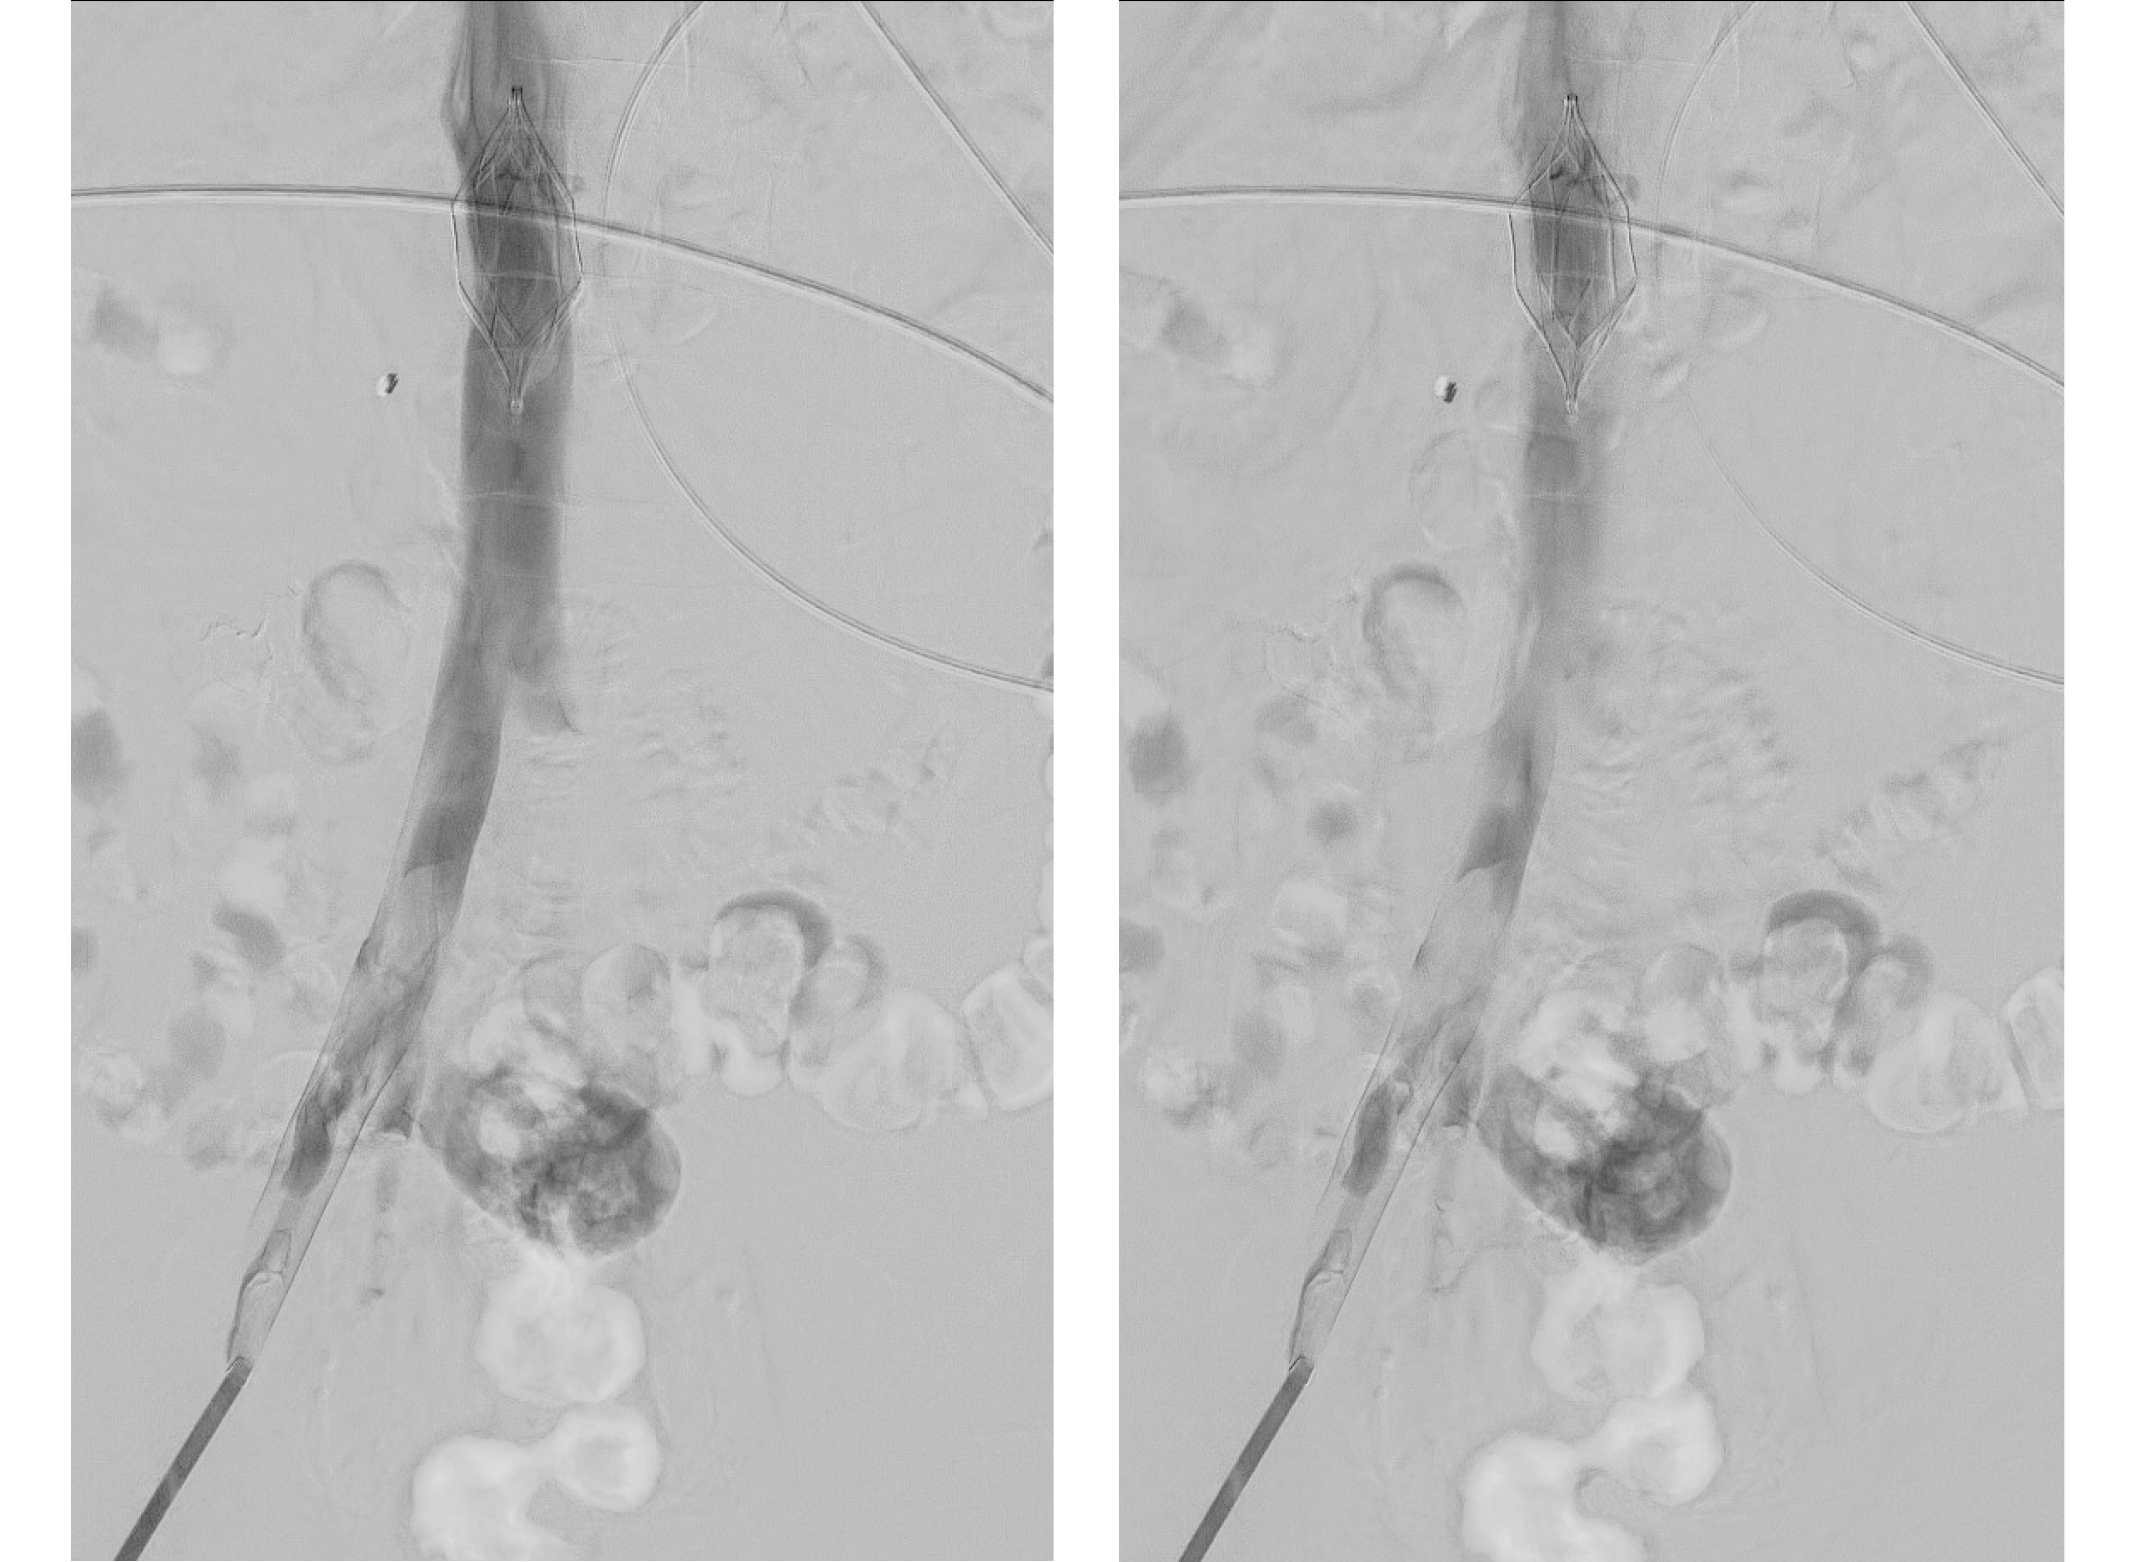

Un día más tarde, el paciente presentó una inestabilidad hemodinámica, descenso de hemoglobina de 30 g/L. Se suspendió momentáneamente la anticoagulación y se realizó una TC abdominal urgente (Figura 3) en la que se observó hemoperitoneo importante, sin signos de sangrado activo. Se colocó un filtro de vena cava inferior (Figura 4) sin incidencias, con el fin de evitar un nuevo evento tromboembólico.

No se objetivó trombosis venosa profunda en las extremidades inferiores mediante ecografía-Doppler, ni en las pruebas de imagen previas a la colocación del filtro de la vena cava (iliocavografía). Al día siguiente, se reinició la anticoagulación, con dosis progresivamente crecientes hasta llegar a dosis terapéuticas sin nuevo sangrado. A los 5 días del ingreso en la UCI, el paciente pudo ser extubado sin incidencias. Durante el ingreso el paciente precisó hemodiálisis por insuficiencia renal aguda. A pesar de las paradas cardiorrespiratorias reiteradas, no sufrió secuelas neurológicas evidentes.

Tras constatar la ausencia de sangrado, se inició tinzaparina a dosis anticoagulantes que se mantiene sin incidencias. A los 20 días, pudo retirarse el filtro de vena cava inferior sin complicaciones.